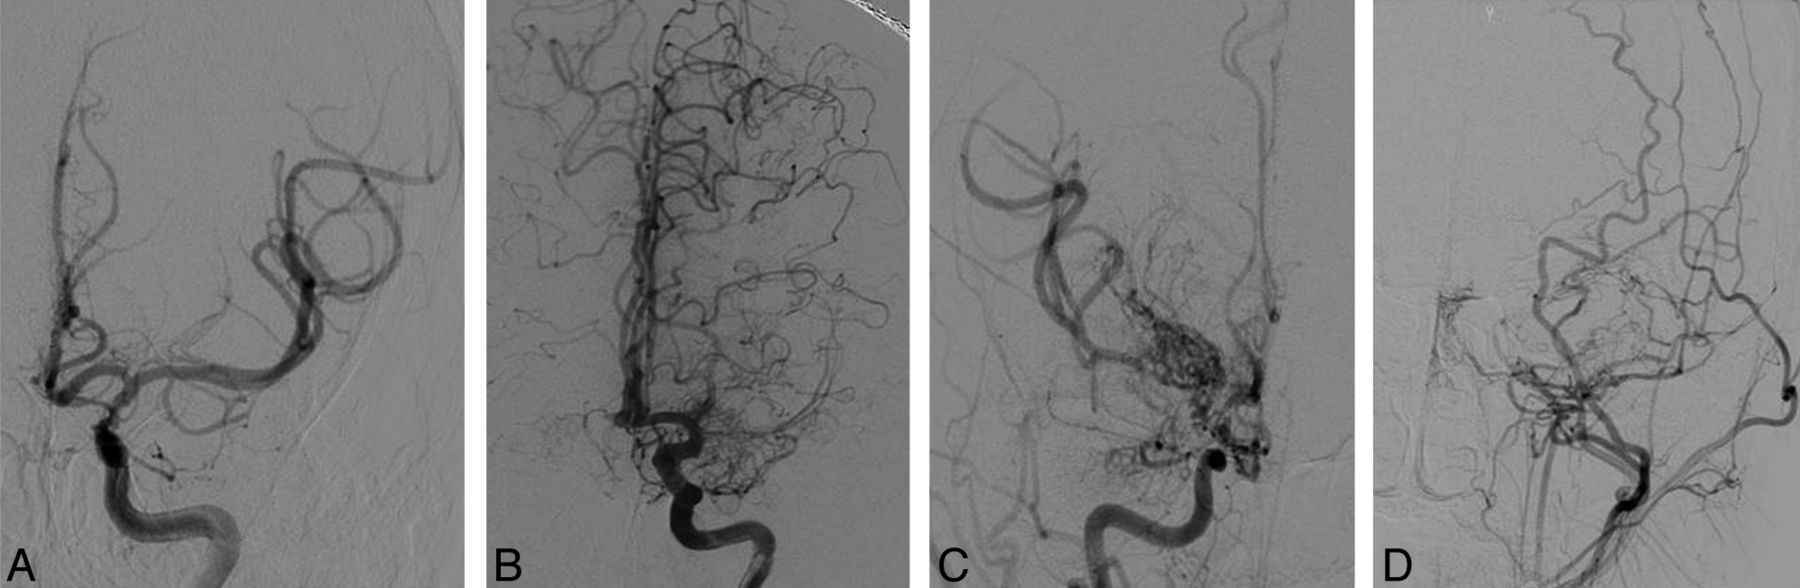

Modified Suzuki scoring

Modified Suzuki scoring. Anteroposterior projections from DSA demonstrate a moderately stenosed left ICA without anterior cerebral artery or MCA involvement or Moyamoya perforators (mSS I) (A); an occluded left M1 with well-developed ICA Moyamoya perforators (mSS II) (B); an occluded right ICA, A1 and M1 with extensive Moyamoya perforators (mSS III) (C); and an occluded left ICA, M1 and A1 with absent Moyamoya perforators (mSS IV)—external carotid collaterals are visualized from a common carotid injection (D).